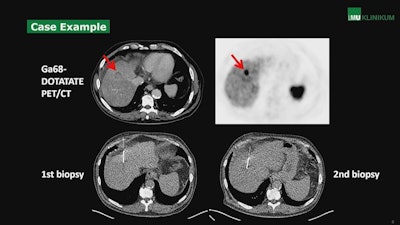

According to the results, SSR-positive metastatic hepatic involvement on PET/CT was reported in 98.6% (n = 145) cases, while histopathology showed hepatic involvement of NETs in 92.5% (n = 136) of cases. In 7.5% (n = 11) of cases, histopathology was negative, despite suspected liver metastases in SSR-PET/CT scans. In addition, in seven of 11 cases in which a second biopsy was available, SSR-PET/CT confirmed findings of liver metastases in five cases, while two of the rebiopsies confirmed the negative histopathologic results, Fabritius noted.

A case from the study showing uptake of the somatostatin receptor (SSR) radiotracer Ga-68 DOTATATE in a metastatic neuroendocrine liver tumor. Image courtesy of Dr. Matthias Fabritius.Ultimately, the positive predictive value (PPV) of SSR-PET/CT for detecting liver metastases was excellent at 92.4%, but even higher at 95.9% when compared with histopathology and rebiopsy, according to the study.